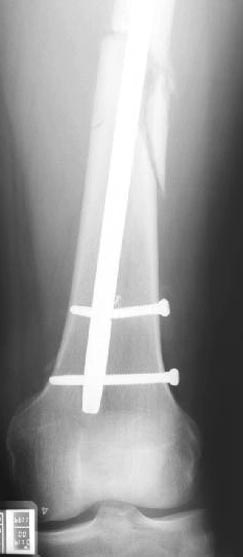

Из истории болезни: два года назад проперирован по поводу 3А открытого перелома бедра, травма на работе в результате "стена упала на него". Сопутствующая травма: Закрытая травма черепа, перелом голеностопного сустава (прооперериван) и перелом плеча (консервативное лечение)

Лечение бедра - ургентное оперативное лечение антеградным с минимально рассверливанием, фиксацией с минимальным диаметром штифта и плюс irrigation and debridment и с закрытием поперечной до 10 см раны на уровне перелома в день поступления.

Снимки представлены: 1 мес; 3 мес; 1 год; 2 года, предоперационные и ротационная КТ грамма

Деформация:

Вальгус- 17 градусов

Рекурватум 5 градусов

Укорочение 2.5см

Ротационно 22 градусов внутренная

Смещение диафиза по поперечнику 75%

Операцию провели в два этапа, сперва удалили штифт, рассверливание римером на пару мм большего диаметра, определение чувствительности на анаэробную и аэробную культуру (где исследования показали негативный результат чувствительности), через дней десять - начали аппаратную фиксацию.